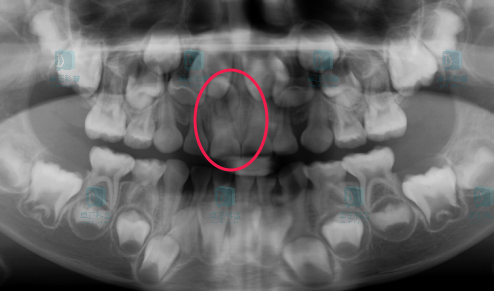

你猜对了,拍片!一般建议在孩子6岁左右开始换牙的时候常规拍一张全口牙片,对牙齿数目、排列、发育情况进行筛查

图片

埋伏倒置多生牙